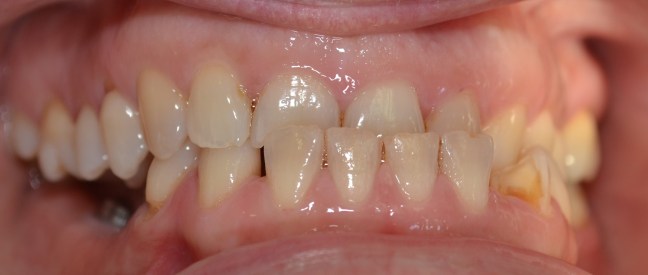

Funkcionális és esztétikai kezelés: harapás korrigálása a fogív kiegyenesítése, fogak közötti rések szűkítése, kereszt harapás megszüntetése az összes megmaradt fog koronázásával. A hiányzó hátsó fogak pótlása implantátumokon megtámasztott koronákkal.

Protetikai munka elkészülésének ideje: 10 munkanap

Koronák anyaga: fémkerámia

Fogszín: A1.